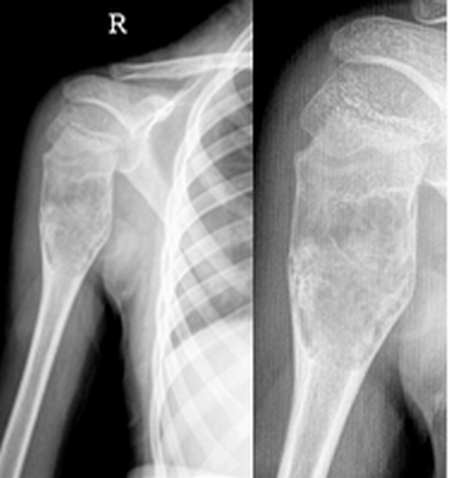

男,11y.

本例显示右肱骨上段干骺端明显膨胀,骨皮质变薄,其内可见不规则网纹状骨性间隔,病灶边缘有轻度硬化,似有骨小梁中断,病变段骨皮质未穿破,无明显软组织肿块及骨膜反应.

意见:右肱骨上段纤维结构不良.

右肱骨干骺端见一呈膨胀性生长的透光区,其内可见骨性间隔,放大图像似可见“骨片陷入”征,骨皮质变薄,病变长轴与肱骨一致,病变未突破骺板,多考虑动脉瘤样骨囊肿

鉴别诊断:骨纤维异常增殖症

右肱骨上段膨胀性占位,肿瘤内有紊乱的骨质和“磨玻璃”样肿瘤组织,考虑骨纤维瘤可能性大。[emb25][emb25]

动脉瘤样骨囊肿为偏心性膨胀,皮质菲薄,程泡沫状改变。支持骨纤

病理结果没有追查到,病人认为是骨纤。毛玻璃样改变,皮质菲薄,发生于干骺端,程膨胀性改变。

骨囊肿持点:密度更低,膨胀性不强。

动脉瘤样骨囊肿特点:偏心性膨胀,膨胀性更强,皮质更薄。

x线表现:右肱骨近骨骺端见有囊状膨胀透亮区,骨皮质明显变薄,其内可见有粗细不一的骨嵴及钙化影,边缘可见硬化缘,外侧似见骨皮质不连续,周围软组织未见明显肿胀。

诊断:右肱骨良性肿瘤或肿瘤样变,考虑内生软骨瘤可能性大。